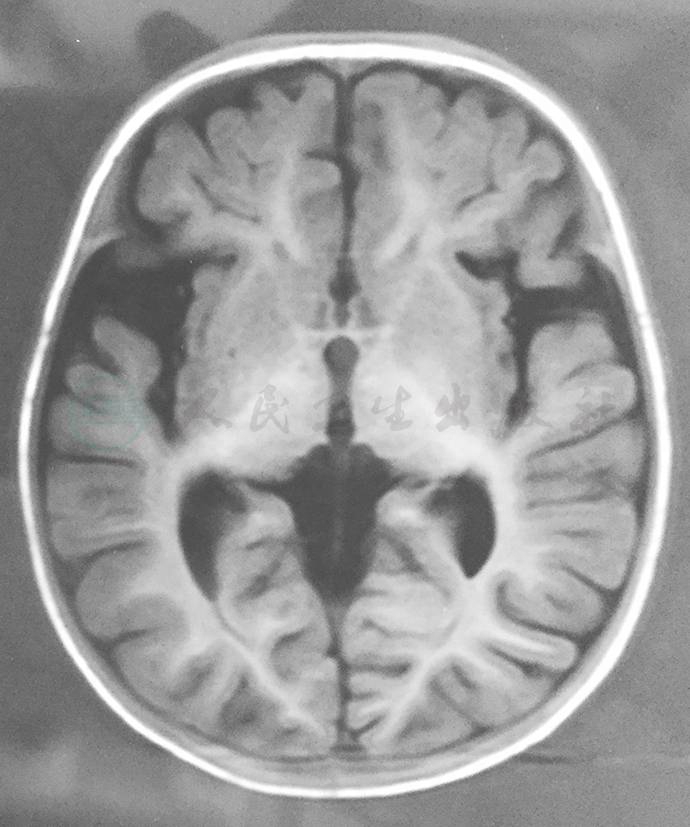

NAAS患儿实验室检查表现为全身炎症指标异常,包括红细胞沉降率(erythrocyte sedimentation rate,ESR)、C反应蛋白(C-reactive protein,CRP)和血清淀粉样蛋白A(serum amyloid a,SAA)升高,急性发作时血白细胞升高,脑膜炎时可有颅内压升高和脑脊液细胞数增多,常出现贫血和血小板增多。超声检查可见淋巴结和肝脾轻度肿大;膝部X线检查可见髌骨肥大/过度生长、骨骺过度生长和关节炎的表现。头颅影像学检查可见脑室扩大、脑萎缩等表现(图2)。

图2 NOMID患儿的头颅MRI